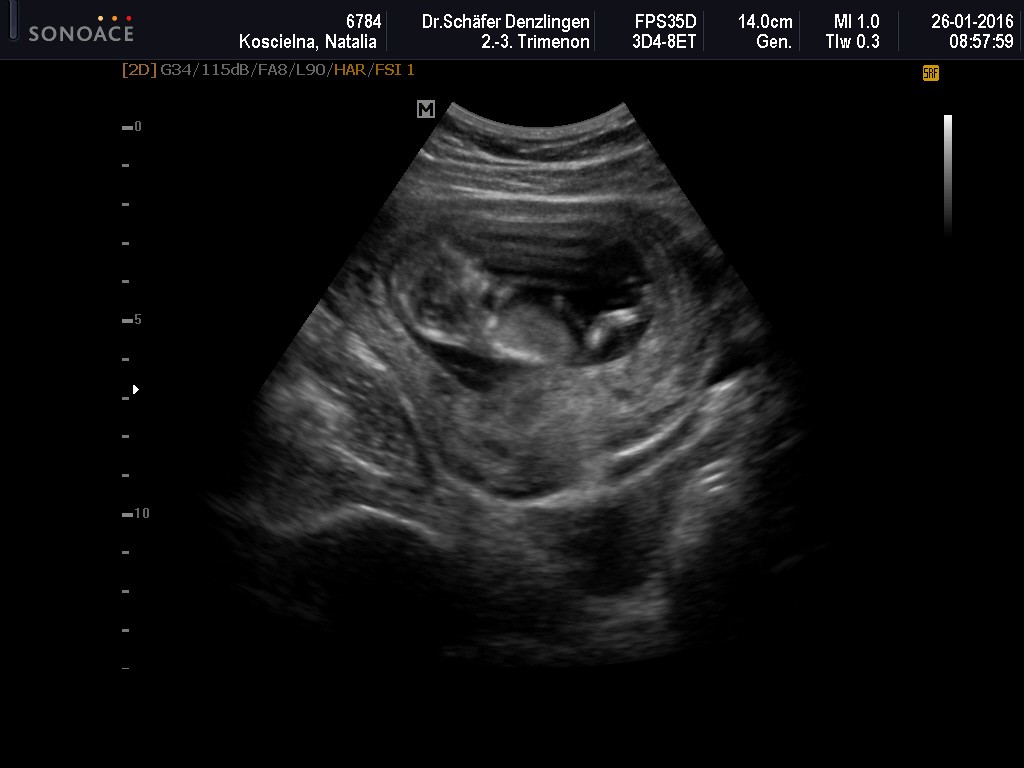

Wczoraj miałam wizytę - wszystko ok, ciąża troszkę większa, bo wszytskie pomiary pokazywały na 12+4, wszystko ok, więc ulga wielka, bardzo długo mi robił usg, mierzył i wszystko ok. Kolejne badania do zrobienia na tokspolazmoze a już sama chciałam sobie robić. Kolejna wizyta za 3 tygodnie. pokazuje zdjęcie z usg, po lewejrączka przy główce, na drugim nóżki i brzuszek![]()

dał mi zdjęcie i mówi :ma Pani swoje nóżki i rączki